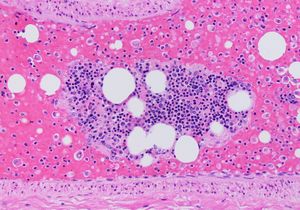

거대 및 부분 거대 폐색전증의 경우, 심장 초음파 검사에서 우심실 기능 부전이 나타날 수 있으며, 이는 폐동맥이 심하게 막혀 우심실이 압력을 감당할 수 없음을 의미한다. 일부 연구에서는 이러한 소견이 혈전 용해 적응증이 될 수 있다고 한다. 모든 PE 의심 환자에게 심장 초음파 검사가 필요한 것은 아니지만, 심장 트로포닌 또는 뇌 나트륨 이뇨 펩타이드 증가는 심장 부담을 나타내어 심장 초음파 검사를 정당화하고[75] 예후에 중요할 수 있다.[76]

심장 초음파 검사에서 보이는 우심실의 특정 모습은 ''맥코넬 징후''로, 중간 자유 벽의 무운동증과 심첨부의 정상적인 움직임이 나타나는 것이다. 이 현상은 급성 폐색전증 진단에 대해 민감도 77%, 특이도 94%를 갖는다.[77]